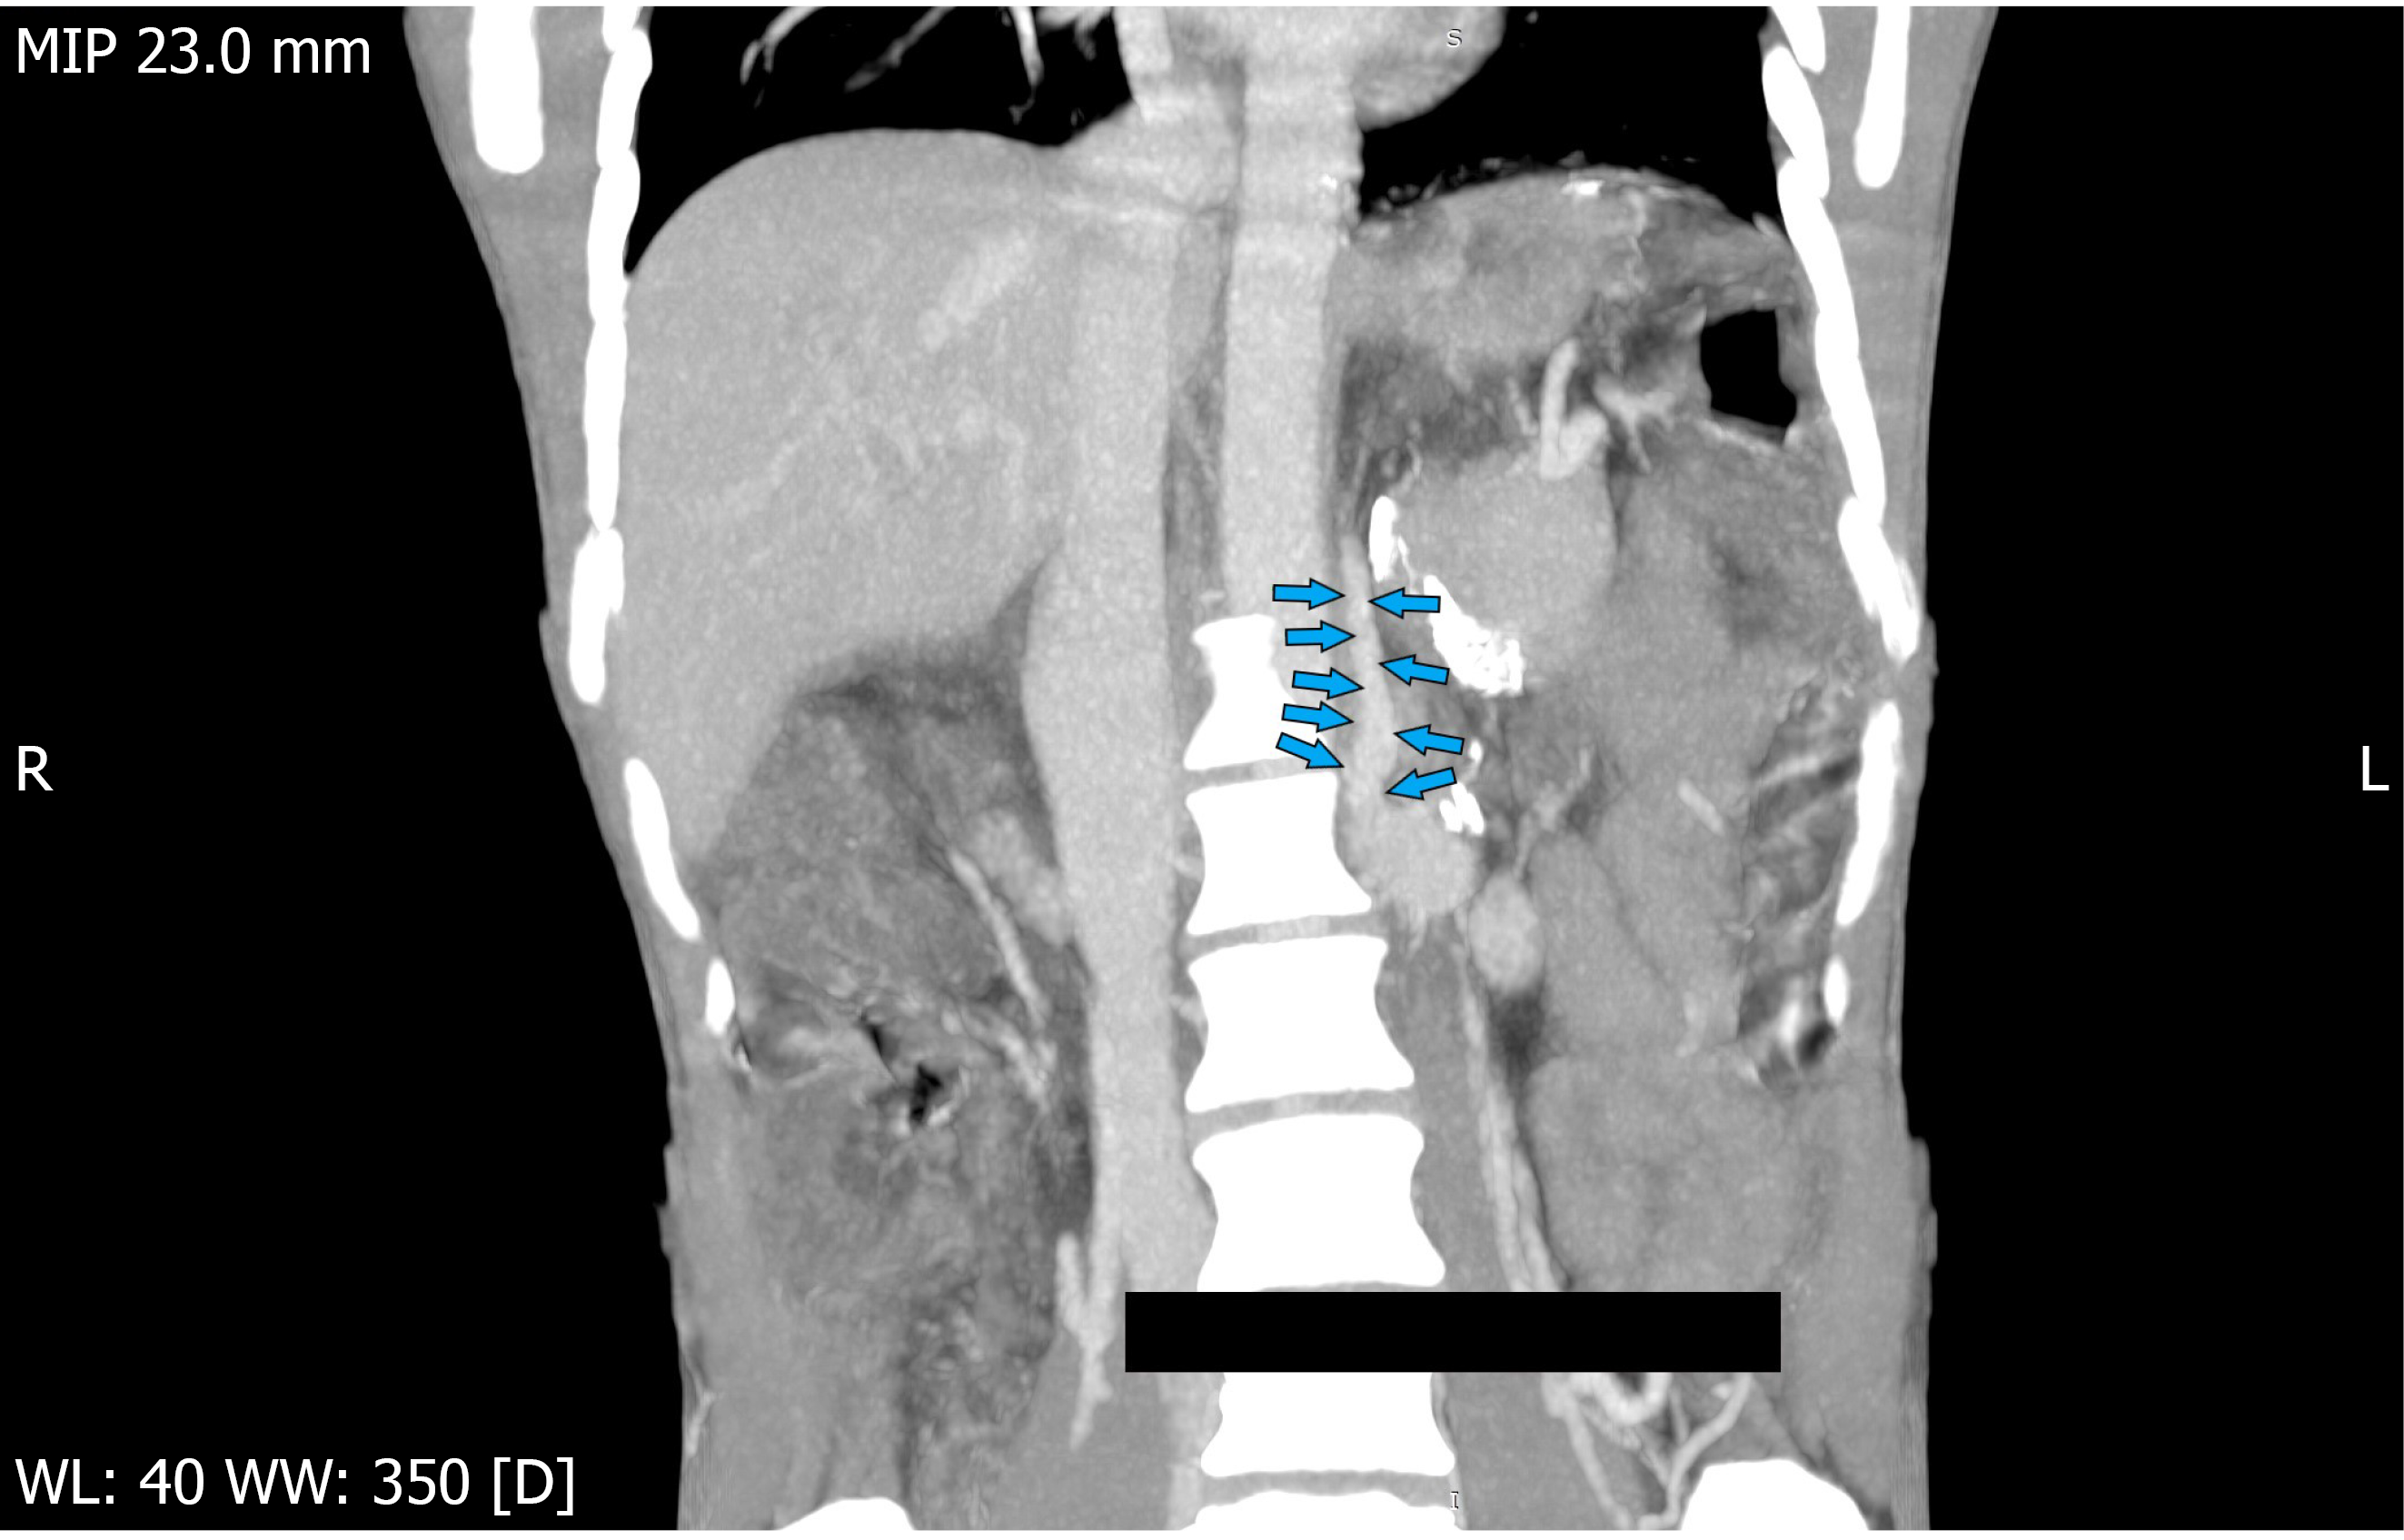

UGIE revealed one column of grade 3 esophageal varix and one GOV2F1 gastroesophageal varix (GOV2F1: Tortuous, extending from the gastric fundus towards the greater curvature) that were treated with endoscopic variceal ligation and endoscopic sclerotherapy (using cyanoacrylate glue injection), respectively. Following the UGIE, he had another episode of seizure with deterioration of sensorium without any focal neurological deficits. He was given intravenous antiepileptics. This was followed by melena along with a drop in hemoglobin. In view of his worsening vital parameters, he was shifted to the Intensive Therapy Unit, intubated, and put on mechanical ventilation. Repeat UGIE revealed no active bleeding sources and confirmed obliteration of gastric and gastroesophageal varices. Non-contrast CT of the head revealed a mega cisterna magna but no evidence of an infarct. CT angiography of abdominal vessels revealed a 6 mm spontaneously developed shunt arising from the left renal vein with obliteration of gastric and esophageal varices and bilaterally enlarged intrahepatic biliary radicles along with closure of the previously created shunt (Figure 1).